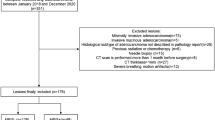

Results

Between January 2004 and September 2015 (the date of patients diagnosed with non-small cell lung cancer ranged from September 2014 to September 2015), 655 patients were diagnosed with lung cancer. The screening criterion was untreated primary lung cancer patients with completed CT and pathological data. There were 220 cases of SCLC (169 cases of central type, 51 cases of peripheral type) and 435 cases of NSCLC (226 cases of central type, 207 cases of peripheral type). In 207 cases of PNSCLC, there were 48 squamous cell carcinomas, 139 adenocarcinomas, seven low differentiated carcinomas, five sarcomatoid carcinomas, one neuroendocrine carcinoma (non-small cell), three adenosquamous carcinomas and four undifferentiated non-small cell lung cancer.

According to the TNM for the 7th edition of the AJCC staging system, there were 11 cases of stage I, 10 cases of stage II, 10 cases of stage III and 20 cases of stage IV in 51 cases of PSCLC; there were 59 cases of stage I, 29 cases of stage II, 31 cases of stage III and 88 cases of stage IV in 207 cases of PNSCLC.